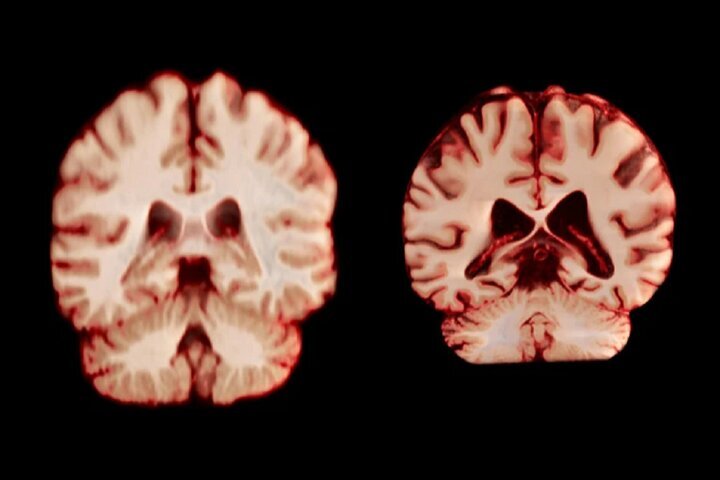

راوندال اضافه میکند که تحقیقات قبلی که تفاوتهای جنسیتی در پیری مغز را بررسی میکردند، نتایج متفاوتی را نشان دادهاند. چندین مطالعه نشان دادهاند که مردان در مقایسه با زنان، کاهش بیشتری در کل ماده خاکستری و اندازه هیپوکامپ را تجربه میکنند، در حالی که سایر تحقیقات، کاهش شدیدتر ماده خاکستری در زنان را گزارش کردهاند.

جدیدترین مطالعه شامل بیش از ۱۲ هزار و ۵۰۰ اسکن مغزی تصویربرداری تشدید مغناطیسی (MRI) از ۴۷۲۶ نفر بود که حداقل دو اسکن برای هر نفر، با فاصله متوسط سه سال انجام شده بود که به بیماری آلزایمر یا هرگونه اختلال شناختی مبتلا نبودند و به عنوان شرکتکننده کنترل در ۱۴ مجموعه داده بزرگتر قرار داشتند. محققان با بررسی عواملی از جمله ضخامت ماده خاکستری و اندازه نواحی مرتبط با بیماری آلزایمر، مانند هیپوکامپ که برای حافظه ضروری است، نحوه تغییر ساختار مغز افراد را در طول زمان مقایسه کردند.

به طور کلی، مردان در مقایسه با زنان، کاهش حجم بیشتری را در مناطق بیشتری از مغز تجربه کردند. به عنوان مثال، قشر پس مرکزی که مسئول پردازش احساسات لامسه، درد و دما و همچنین موقعیت و حرکات بدن است، در مردان سالانه ۲.۰ درصد و در زنان سالانه ۱.۲ درصد کاهش یافت.